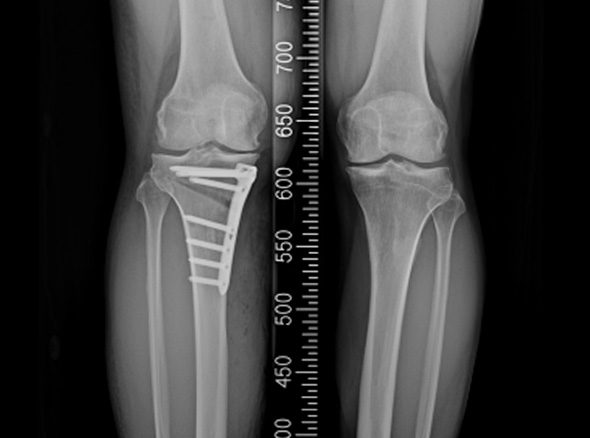

관절내시경을 이용하여 연골재생이나 연골판에 필요한 치료를 시행한 후 경골(무릎 아래 뼈)의 근위부의

계획한 위치까지 절골을 시행한 후 뼈의 탄성을 이용하여 벌립니다. 그리고 금속판과 나사로 고정하여

수술 전 계획했던 X자형 또는 1자형 다리를 만들고 빈 공간에 뼈를 이식하여 골유합을 유도합니다.